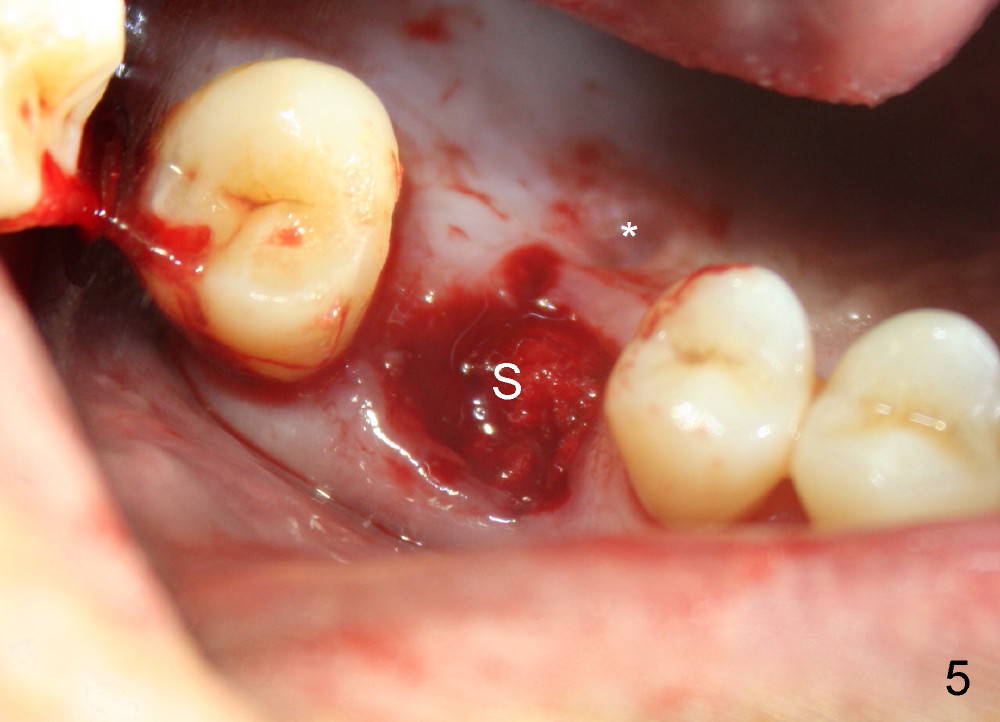

The upper right 1st molar of a 48-year-old man has severe perio endo disease (Fig.1 #3); the bone height for immediate implant (Fig.2) is about 3.5 mm (Fig.1 vertical line). There is a buccal (Fig.3 B) abscess (*); the palatal (Fig.4 P) root is exposed. After extraction, the socket available for immediate implant (Fig.5,6 S) is buccal (without septum), whereas the apex of the palatal root is far away from the main socket. In fact there is an advantage: the socket is smaller. Osteotomy is created in the main socket as palatal as possible, using osteotomes, reamers and taps (Fig.7 T). The sinus floor is lifted (Fig.7 ^). When 7x17 mm implant is placed (Fig.8 I), the insertion torque is >60 Ncm. The remaining socket (Fig.8 *) is to be packed with mixture of autogenous bone, allograft and synthetic bone (Osteogen) (Fig.9,10 <). Immediate insertion of an abutment (Fig.8-10 A) helps retain perio dressing (Fig.11,12). No collagen membrane is used in this case to cover the bone graft before placement of perio dressing. Postop the patient cannot tolerate oral Amoxicillin because of stomach upset. The dose is reduced. Two weeks postop, the perio dressing is stable, but discolors (Fig.13). When the dressing is removed, the buccal bone graft is exposed, which is not abnormal. What is unusual is discoloration (Fig.14). The significance of the latter is not revealed until 3 months postop when the patient remains asymptomatic, but there is an apical fistula (Fig.15 <). There is a communication between the fistula and the buccal sulcus of the implant: water passing freely. Based on the position of the buccal plate of the neighboring teeth (*), the buccal plate of the implant should be lost, which is consistent with finding of PA (Fig.16, as compared to Fig.8). Guided bone regeneration seems necessary.